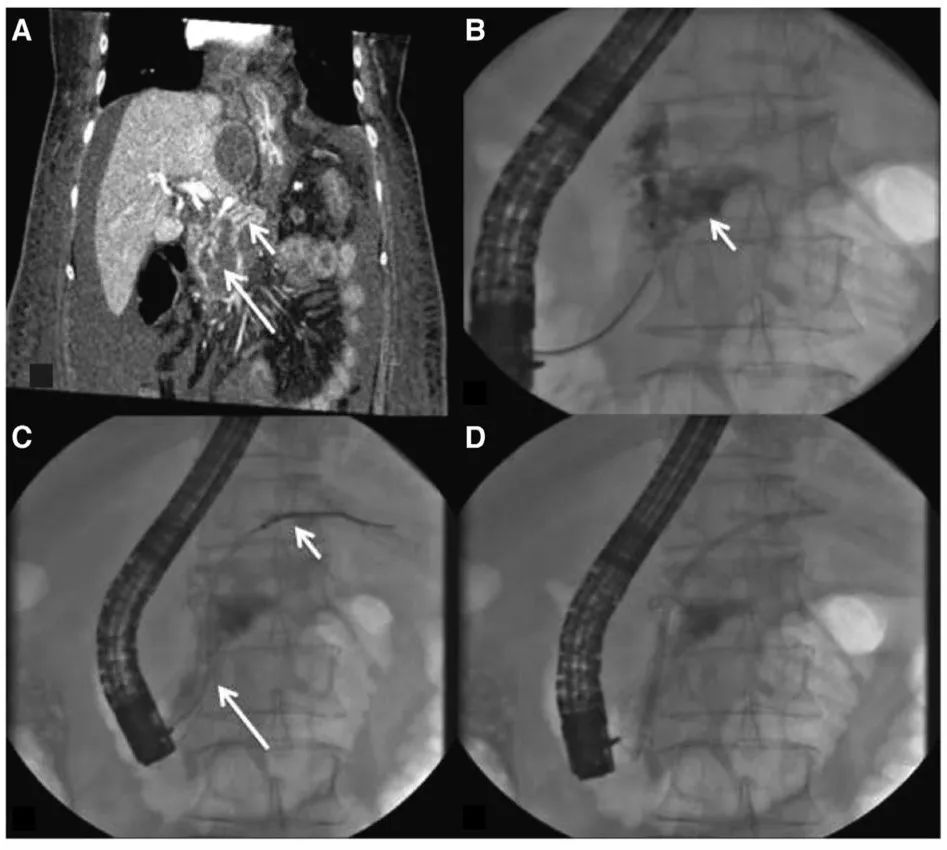

操作一般为细针穿刺抽吸、置入导丝、扩张、放置支架,操作过程中保持镜身的稳定是十分重要的。引流操作过程中一般需要对造瘘口进行扩张(图2),以允许放置支架或通过镜身。扩张至4-8mm可以进行塑料支架和金属支架的置入,扩张至15mm可以允许通过9mm的胃镜,如果计划进行治疗性操作(如EN),那么需要扩张至18-20mm。

权威研究说,胰腺液体积聚引流,内镜可以这样用

图2 扩张造瘘口